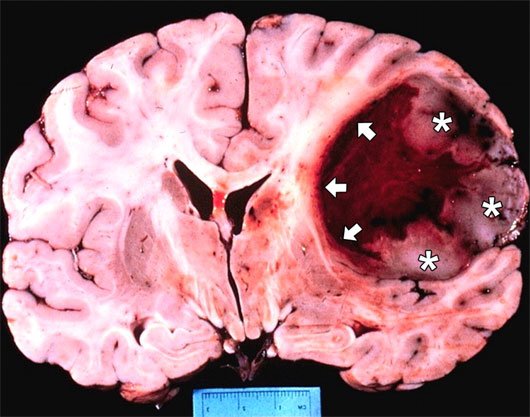

Kết quả chụp cộng hưởng và xét nghiệm tại Bệnh viện K cho thấy, anh B. có khối u não nền sọ vùng dốc nền có kích thước lớn 3 x 4cm. Khối u lớn này liên quan đến nhiều chức năng quan trọng như: Thân não, mạch máu não, tuyến yên, và ở đáy sọ.